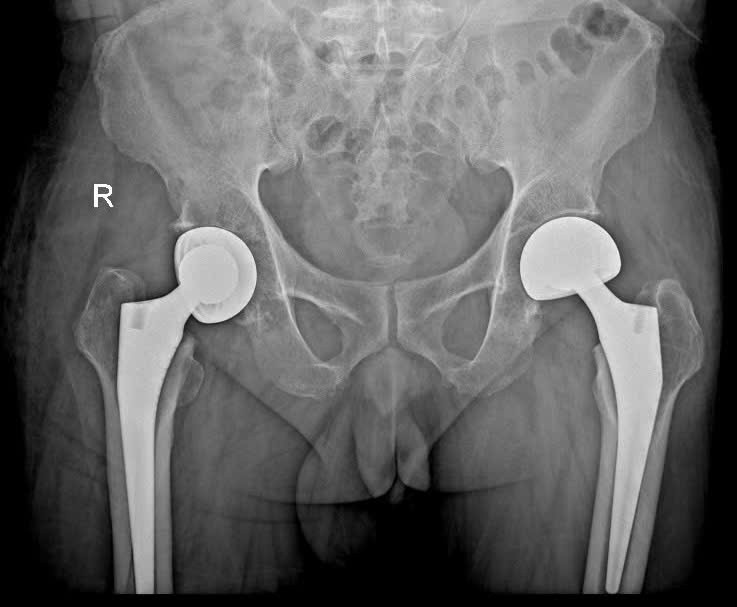

Theo các bác sĩ chuyên khoa, phẫu thuật thay khớp háng là phương pháp điều trị tối ưu cho các trường hợp gãy cổ xương đùi, thoái hóa hay hoại tử khớp háng khi điều trị nội khoa không còn hiệu quả. Đây là kỹ thuật phức tạp, đòi hỏi phẫu thuật viên có tay nghề cao cùng hệ thống trang thiết bị hiện đại.

Hình XQuang bệnh nhận đã thay khớp háng bên phải |